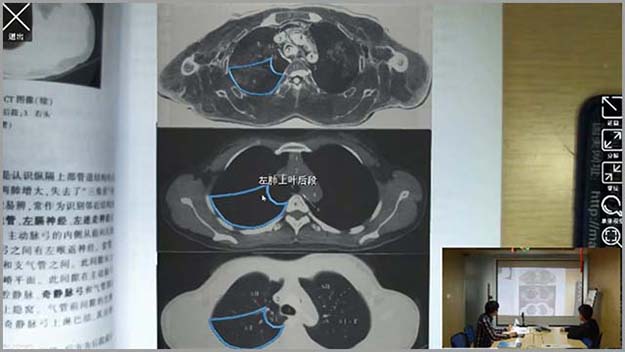

基礎醫(yī)學系列-增強現(xiàn)實醫(yī)學影(yΩ↑∏πǐng)像應用(yòng)解剖學

增強現(xiàn)實醫(yī)學影(yǐng)像應用(yòng)解剖學